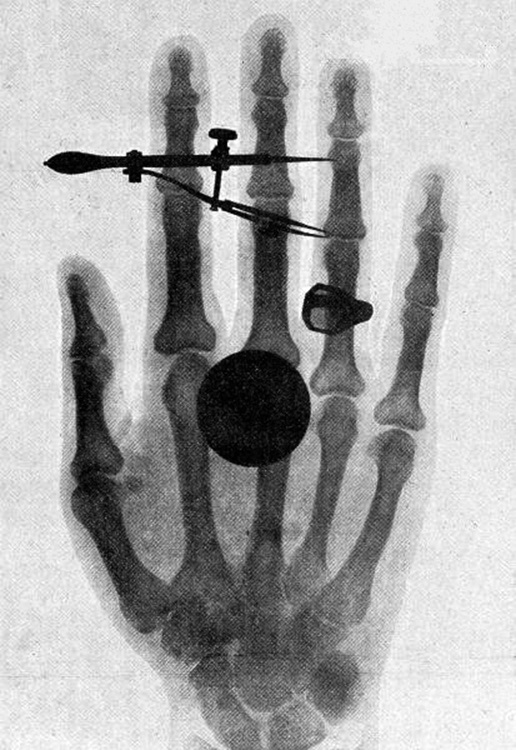

At lower photon energies, x rays are not as penetrating as \(\gamma \) rays and are slightly less hazardous. X rays are ideal for medical imaging, their most common use, and a fact that was recognized immediately upon their discovery in 1895 by the German physicist W. C. Roentgen (1845–1923). (See this figure.) Within one year of their discovery, x rays (for a time called Roentgen rays) were used for medical diagnostics. Roentgen received the 1901 Nobel Prize for the discovery of x rays.